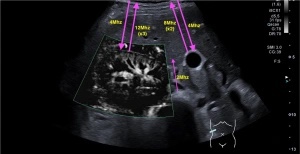

Si utilizamos frecuencias bajas (entre 2 y 6 MHz), tenemos que usar una sonda cónvex, y estudiaremos estructuras con profundidades grandes, Abdómenes y Ginecológicas.

Si usamos frecuencias altas (entre 10 y 18 MHz), utilizamos sonda lineal y serán objeto de estudio estructuras superficiales como, Músculos, Tendones, Ligamentos, Partes Blandas, Tiroides y Cuello, estructuras vasculares superficiales, Testes, Mama, Ojos, etc…Muy versátiles, por tanto, estas frecuencias altas. Incluso, podemos usar éstas en ecografía pediátrica, si la/el paciente es suficientemente pequeño, por ejemplo, es muy normal realizar ecografía de Caderas, Transfontanelar y Abdomen a bebés, y estas frecuencias altas son ideales.

Para realizar el estudio de un músculo, por ejemplo, usaremos, dentro de las frecuencias altas, la más alta si el músculo es muy superficial, pero si el músculo es más profundo y/o el paciente es muy voluminoso quizá sea bueno bajar un salto de frecuencia, así ganaremos un poco más de visión profunda aunque perdamos un poco de resolución o nitidez.

Dentro de las frecuencias altas y bajas podemos elegir entre varias, eso es debido al Ancho de Banda…Es decir, para frecuencias bajas, por ejemplo para hacer un abdomen, usaré frecuencia de 3 mHz si en paciente es obeso (mucha profundidad) y 5 mHz si el paciente es muy delgado (poca profundidad), o de otra manera, mi sonda cónvex (baja frecuencia) puede usar varias frecuencias bajas en función de las necesidades del estudio. De otro modo, el ancho de banda es una horquilla de frecuencias que puedo usar dentro de un tipo de frecuencias, bien sean altas o bajas. Un ejemplo de esto lo tenemos en las imágenes siguientes.

Otro ejemplo…para hacer un hombro, usaré frecuencia alta de 12 mHz si en paciente es muy musculoso (mucha profundidad) y 18 mHz si el paciente es muy delgado (poca profundidad), o de otra manera, mi sonda lineal (alta frecuencia) puede usar varias frecuencias altas en función de las necesidades del estudio.

Por ejemplo en algunas patologías es muy útil el cambio de frecuencias, por ejemplo en los hígados con Esteatosis Hepática donde no se observa bien los planos más profundos del órgano afectado. En la imagen siguiente podemos ver como disminuyendo la frecuencia ganamos poder de penetración pudiéndose observar en la profundidad con más claridad la interfase producida por el diafragma (línea blanca hiperecogénica o brillante).